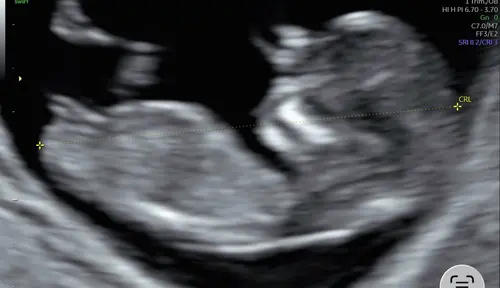

Ik vind het wat lastig om met zekerheid te zeggen of het witte streepje de nub is. Maar als dat de nub wel is, dan zeg ik ook een meisje!

NUB vrijwel parallel aan de ruggengraat = meisje 🩷 maar beter tussen de 12 en 13 weken in te schatten, er is hier op t forum een groot topic over waar een account ‘Nubster’ met bijna zekerheid het voor je kan voorspellen 🔮😄😁

Ook vrijwel parallel aan ruggengraat 🩷

Misschien is de echo niet strak genoeg. Maar mijn gevoel zegt een meisje! Wat denken jullie?👀💕